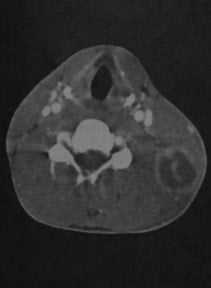

Септический гранулематоз у мужчины 27 лет. КТ с контрастированием: крупный округлый абсцесс с интенсивным усилением стенки, расположенный позади левой грудино-ключично-сосцевидной мышцы. Плотность в полости абсцесса снижена, выявляются перегородки.

КТ с контрастированием: занижнечелюстной абсцесс на уровне угла нижней челюсти слева с множественными внутренними перегородками. Наблюдается характерное снижение плотности в центре абсцесса (жидкость) и усиление стенок. Отек тканей, окружающих абсцесс.